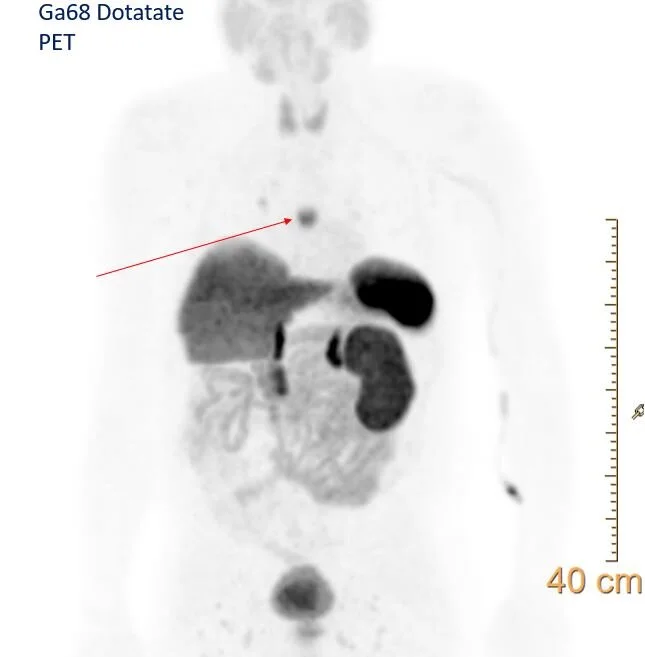

Dotatate scan: The nodule shows uptake, consistent with neuroendocrine tumor. Note physiologic uptake in the spleen, adrenals and kidneys, as well as uncinate process of pancreas.

Fusion image confirms uptake in the subcarinal nodule.